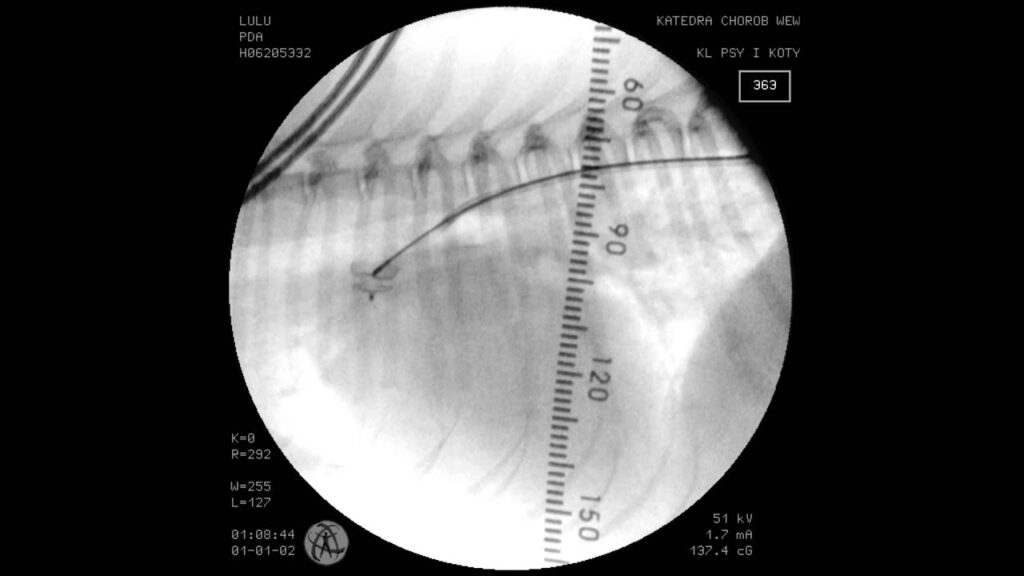

Proceduren udføres af en specialiseret veterinær kardiolog under fuld narkose og med brug af røntgengennemlysning (fluoroskopi).

- Vaskulær Adgang og Angiografi: Der laves et lille snit i lysken for at få adgang til en af de store pulsårer (arteria femoralis). Et tyndt rør (et kateter) føres herfra op til hjertet og ind i aorta. Der sprøjtes en lille mængde kontrastvæske ind for at lave et angiogram – en røntgenfilm af blodkarrene. Dette giver kardiologen mulighed for præcist at se PDA'ens form og måle dens smalleste punkt, den minimale duktale diameter (MDD).

- Placering af ACDO: ACDO-enheden foldes sammen og føres gennem et leveringskateter op til PDA'en. Først foldes den flade, distale skive ud i lungepulsåren. Derefter trækkes hele systemet forsigtigt tilbage, indtil skiven ligger an mod åbningen af PDA'en. Mens enheden holdes stabilt, trækkes leveringskateteret tilbage, hvilket får taljen til at folde sig ud inde i selve PDA'en og den kopformede, proksimale skive til at folde sig ud i den brede ende af PDA'en (ampulla).

- Bekræftelse og Frigørelse: Kardiologen tester enhedens placering og stabilitet ved forsigtigt at skubbe og trække i det kabel, den er fastgjort til. Når positionen er bekræftet som perfekt, afkobles enheden fra kablet. Blodplader og koagulationsfaktorer vil hurtigt danne en prop omkring enheden, hvilket fører til fuldstændig lukning.

- Afsluttende Kontrol: Et sidste angiogram udføres for at bekræfte, at der ikke længere er blodgennemstrømning gennem PDA'en. Hunden overvåges nøje under opvågning og kan ofte komme hjem samme eller næste dag. Opfølgende ekkokardiografier efter 1 dag og 3 måneder bekræfter den fortsatte succes.